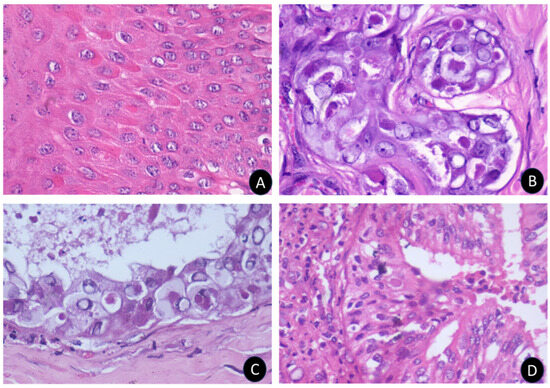

Figure 5. The histopathological changes in different organs of sheeppox disease. The sheeppox cells are identified by a conspicuous intranuclear vacuole with margination of chromatin and inclusion bodies in the skin (A), apocrine gland (B), epidermal cells (C), and lung (D) with pneumocytes.

Microscopic examination of scab lesions revealed necrotic cellular debris entrapped within a coagulated mass. Eosinophilic inclusion bodies of various sizes were present in most scabs, along with micro-abscesses, showcasing the localized inflammatory response and viral replication (Figure 4). The macules or papules displayed epidermal acanthosis, hyperkeratosis, and parakeratosis (Figure 4). The hyperplastic epithelium varied in thickness and showed vacuolation in the stratum spinosum layer, with margination of the chromatin and presence of intracytoplasmic eosinophilic inclusions, referred to as sheeppox cells or ‘Cellules claveleuse’ (Figure 5).

In the dermis, perifolliculitis was a notable feature, characterized by the infiltration of either polymorphonuclear or mononuclear cells involving multiple follicles, accompanied by concentric connective tissue proliferation. Many cells in this area contained eosinophilic intracytoplasmic inclusions of various sizes and shapes, further confirming the viral etiology of the lesions (Figure 5).

The microscopic examination of sheeppox-affected sheep revealed significant alterations in the skin epithelium, with keratinocytes and subepidermal layers being the primary sites of infection. This led to hyperplasia and granulomatous inflammation, consistent with findings from previous studies [24,28,31,32]. The development of pox lesions across various skin locations can be attributed to the epitheliotropic nature of the virus, which targets epithelial cells, causing pathological changes due to viral replication. The formation of papules, attributed to the proliferation of keratinocytes and subepidermal edema, results in the elevation of these lesions above the level of the surrounding skin. These papules often merge to form firm nodules [7], indicating the presence of both vesicular and nodular forms of sheeppox in the observed cases.

This study suggests the coexistence of the classical vesicular form and the nodular form of sheep pox within Karnataka, aligning with documentation from other regions globally [33]. The observed hyperplastic changes are linked to the virus’s encoding of genes homologous to epidermal growth factor (EGF) proteins [34,35], indicating a potent form of the pox virus epidermal growth factor homolog. This Capripoxvirus’s characteristic epitheliotropic behavior, where it multiplies within the cytoplasm of epithelial cells, underscores the complex interaction between the virus and host cell machinery, leading to the varied clinical manifestations observed in affected animals.

This study recorded instances of sheeppox virus-induced vasculitis, perivasculitis, and perifolliculitis, highlighting the virus’s capacity to induce widespread inflammatory responses in infected sheep [24,31]. Notably, the hair follicular cells displayed significant pathological changes, including severe vacuolization, margination of nuclear chromatin, and the presence of eosinophilic cytoplasmic inclusions, characteristic features of cells infected by the sheep pox virus. These observations are in line with previous reports [36], which similarly identified such cells as indicative of sheeppox infection.